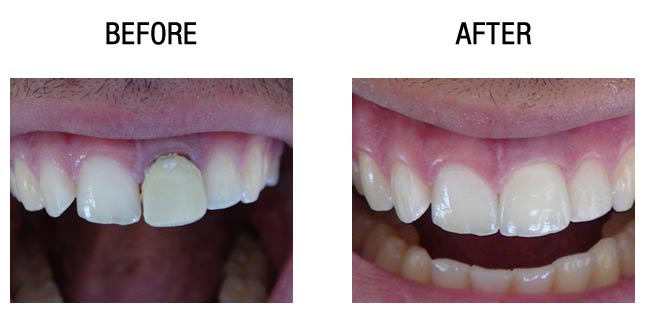

种植牙前后对比

种植牙前后对比